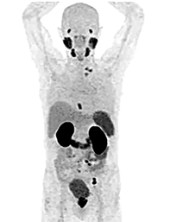

Australia is a world leader in the diagnosis of prostate cancer. Clinical guidelines used worldwide recommend a standard process for diagnosing prostate cancer that comprises prostate-specific antigen (PSA) blood testing followed by a random transrectal ultrasound-guided (TRUS) prostate biopsy procedure if the PSA test result is elevated.1 For many reasons this process is no longer best practice, and Australian practice is evolving ahead of the guidelines. Australian urologists and oncologists are adopting new imaging techniques, including prostate-specific membrane antigen positron emission tomography (PSMA PET) scanning (Figure 1), which is discussed below.